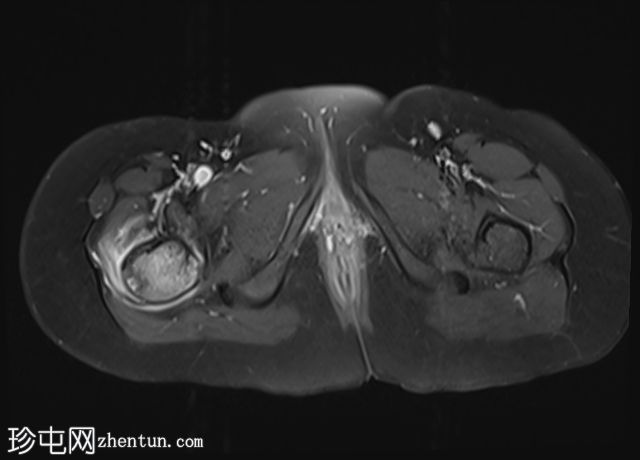

髋部

MRI

轴向

T1

轴向PD

脂肪饱和度

轴向T1

C+脂肪饱和度

右上股骨大转子正下方外侧皮质区可见一小的皮质基部病变,边缘呈低信号,大小约为0.7 x 0.7厘米。

邻近的股骨近端骨干和股骨颈有水肿。

水肿有扩散至邻近肌肉的迹象。